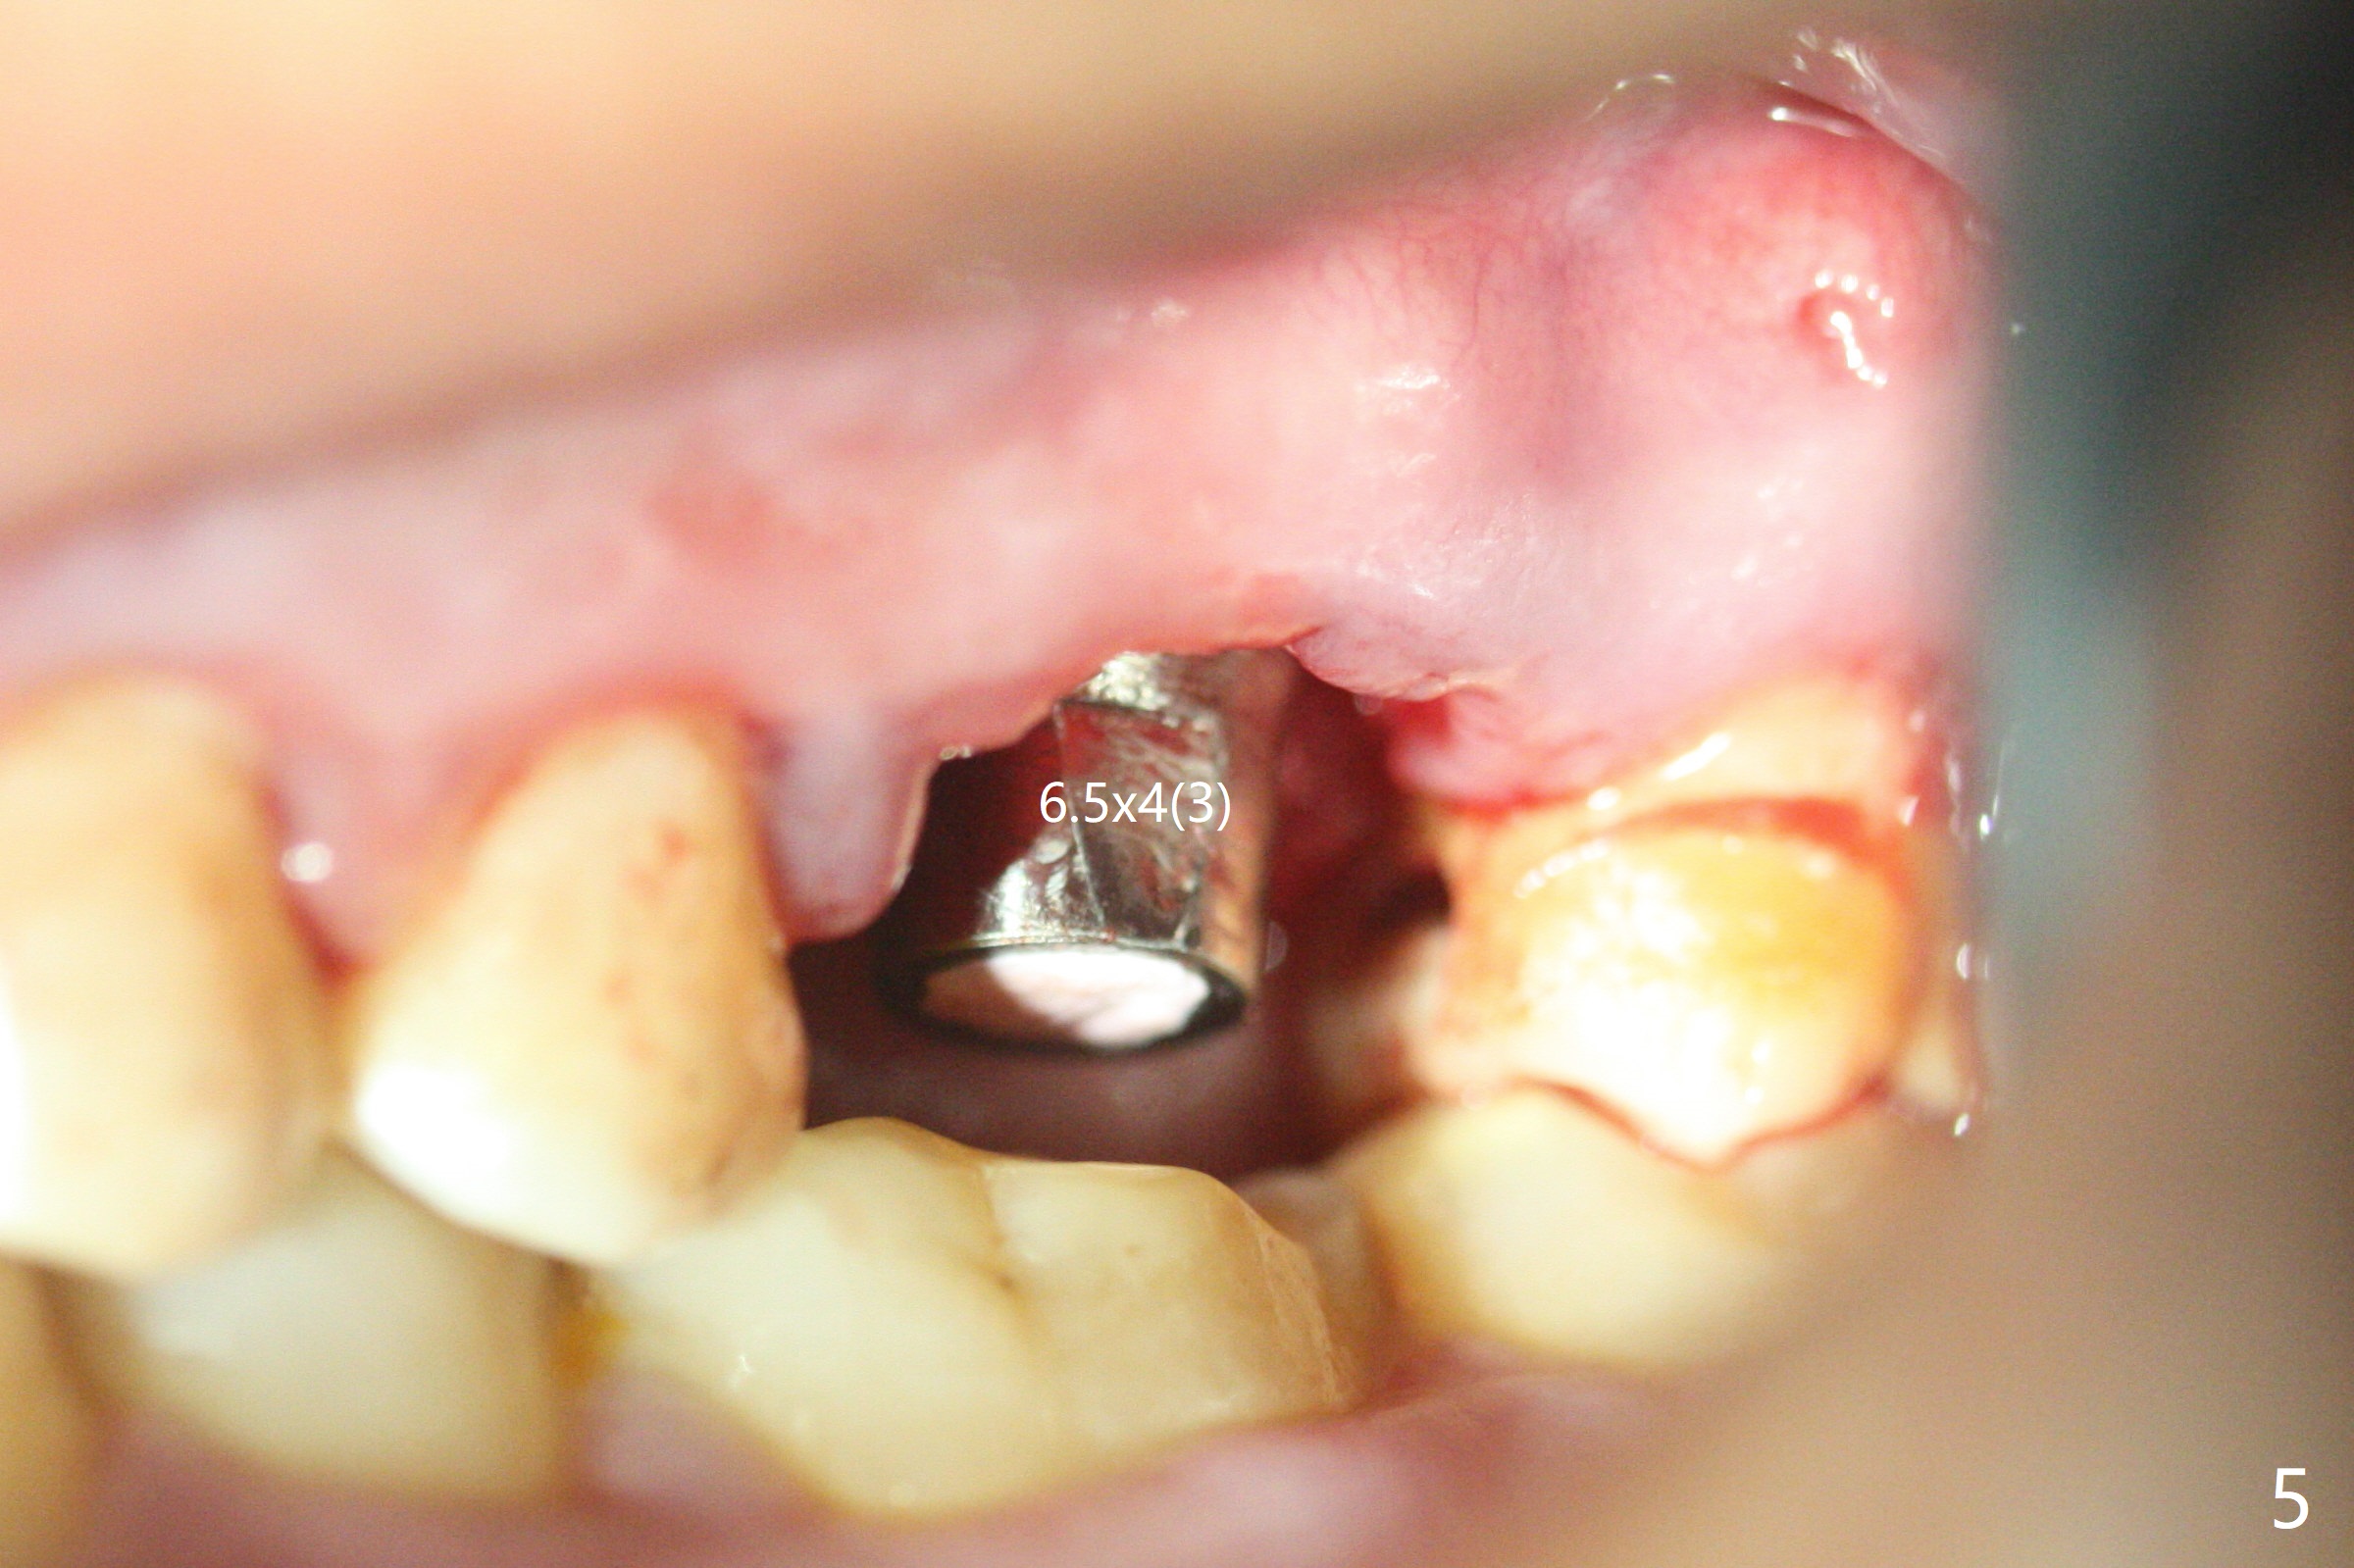

With modification of drill sequence in the last 3 steps (4.5x7.3, 4.0x8.5 and 3.5x10 mm drills) at #14 and sinus lift (Fig.1), a 5x9 mm implant is placed with ~ 50 Ncm following back up twice. Sticky bone mixed with autogenous bone (Fig.1,2 white *) is placed in the sockets before and after placement of a 6.5x5.7(2) mm abutment. Since the palatal gingival margin is recessive (Fig.3 ^), a palatal socket shield retains to prevent further recession (Fig.4 in the end of periodontal probe). Because the margin of the abutment is low, it changes to one with longer cuff (Fig.5). An immediate provisional is fabricated (Fig.6,7 P). The bone graft is indistinguishable from the original alveolus 9 months postop (Fig.8 *). The palatal socket shield is exposed 10 months postop (Fig.9 <). Since the implant is intentionally placed buccal; the sheath is not essential.